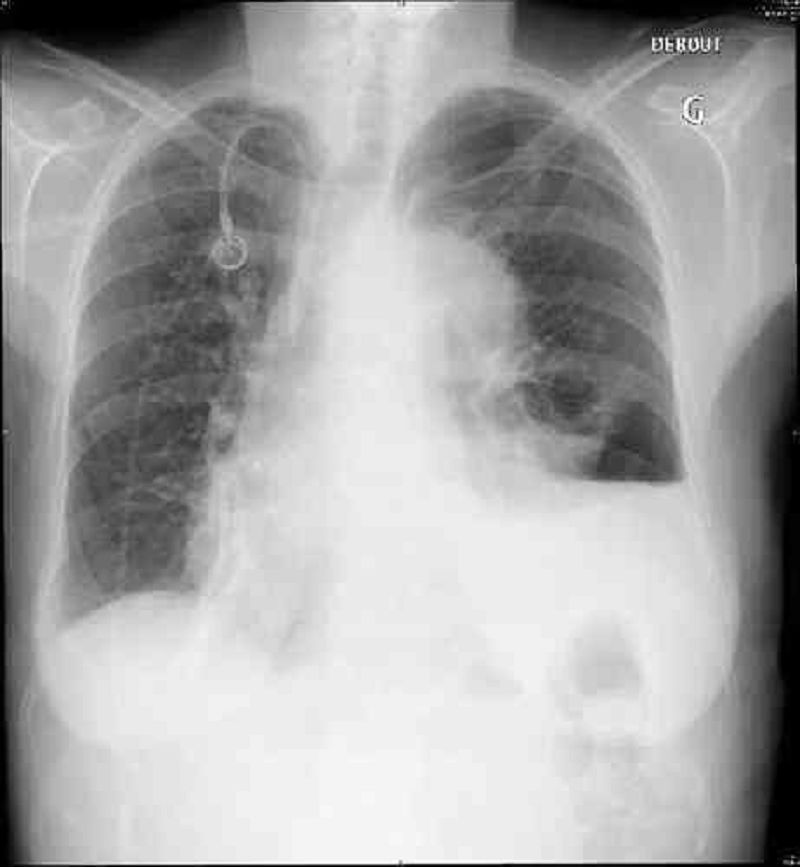

Vous voyez en consultation en urgence une patiente de 35 ans, pour douleur thoracique. Elle est suivie habituellement pour un cancer du sein. A l’examen clinique vous retrouvez une tension à 125/70 mmHg, une fréquence cardiaque à 65/min et une saturation à 96%. L’auscultation pulmonaire retrouve une diminution du murmure vésiculaire de la base gauche. Vous faite une ponction pleurale exploratrice. Le cliché pulmonaire de contrôle est le suivant.Quelle est votre prise en charge en urgence ?

Drainage thoracique

Oxygénothérapie

Exsufflation à l’aiguille

Surveillance simple

Ventilation non invasive